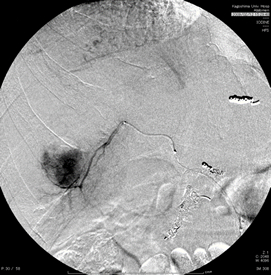

血管造影検査を用いた肝細胞癌に対する肝動脈化学塞栓療法。

カテーテルを腫瘍濃染の近くまで進めて塞栓しています。